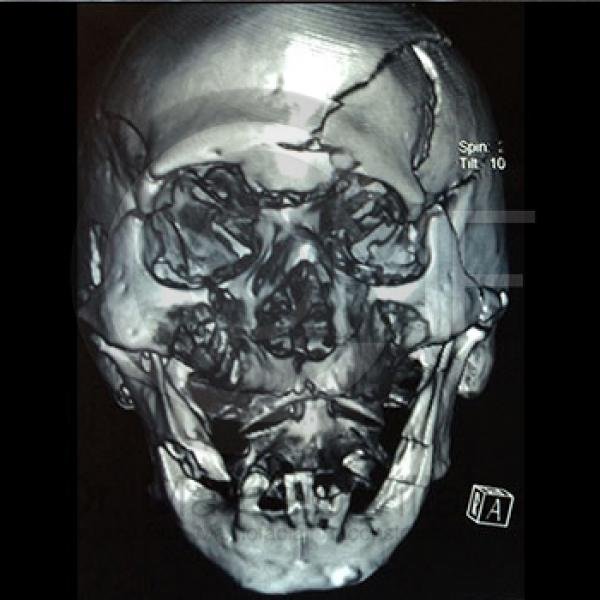

La Cirugía Oral y Maxilofacial es una de las especialidades odontológicas que brinda la posibilidad de ofrecer soluciones medicas y quirúrgicas a diferentes problemas de salud, entre los que se encuentran los defectos congénitos como el labio y paladar fisurados, las disarmonias del desarrollo facial, los traumatismos y lesiones patológicas de la región oral y maxilofacial por mencionar algunos; utilizando distintos procedimientos como la Cirugía Ortognática, la Reconstrucción mediante toma y colocación de injertos, distractores osteogénicos, regeneración tisular, implantes, etc.

Contenido Sensible y Gráfico

Si usted no pertenece al área de la salud, las imágenes pueden ser muy explícitas.